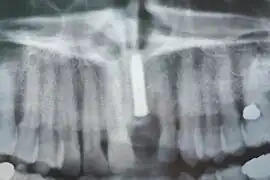

Radiographie des six implants

Contrôle de la cicatrisation à une semaine de l'intervention